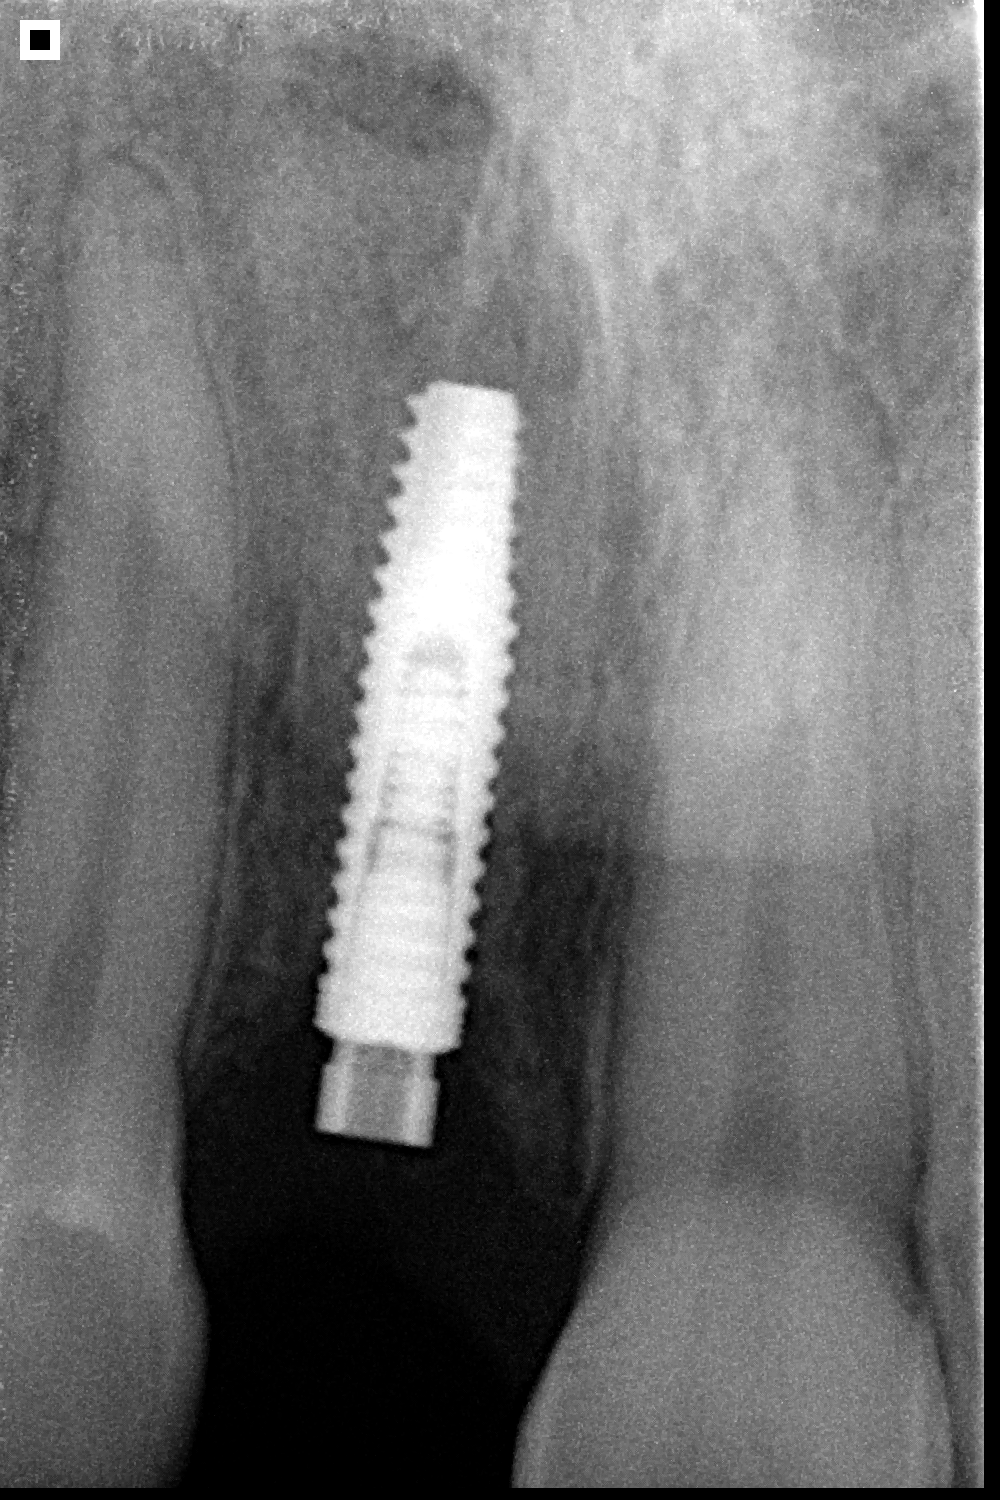

UNITITE PRIME

Indicado para carga inmediata, precoz o tardía: Unitite ha sido diseñado para situaciones desafiantes.

Cicatrización de alta calidad: La cicatrización híbrida de Unitite elimina la fase catabólica de remodelación ósea interfacial en la mayor área del implante, lo que acelera el proceso de cicatrización y mejora la calidad del tejido óseo formado.

Alta hidrofilia: Con una capa de aproximadamente 20nm de hidroxiapatita, el Unitite amplía la actividad de las proteínas que participan en el proceso de osteointegración.

La macrogeometría exclusiva asegura la precisión entre el sistema de fresado y el diseño de las roscas externas, combinando alta estabilidad y disminuyendo la compresión del tejido óseo de cicatrización periimplantaria.

Con microespiras de 0.2 a 0.5 mm, Unitite interacciona con el tejido óseo y alta resistencia mecánica.

DIÁMETROS UNITITE PRIME

3.5, 4.3, 5.0mm

LONGITUDES UNITITE PRIME

8.5, 10.0, 11.5, 13.0, 15.0mm